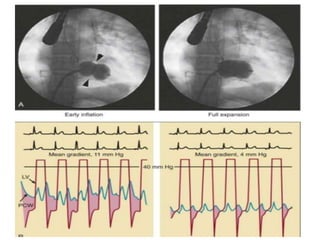

• This percutaneous technique consists of advancing a small balloon

flotation catheter across the interatrial septum (after transseptal

puncture), enlarging the opening, advancing a large (23- to 25-mm)

hourglass-shaped balloon (the Inoue balloon), and inflating it within

the orifice

• This percutaneoustechnique consists of advancing a small balloon flotation catheter across the interatrial septum (after transseptal puncture), enlarging the opening, advancing a large (23- to 25-mm) hourglass-shaped balloon (the Inoue balloon), and inflating it within the orifice • Alternatively, two smaller (15- to 20-mm) side by side balloons across the mitral orifice may be used. • A third technique involves retrograde, nontransseptal dilation of the mitral valve, in which the balloon is positioned across the mitral valve using a steerable guidewire.

• #100 Percutaneous balloon mitral valvotomy (BMV) for mitral stenosis using the Inoue technique (see Chap. 59). A, The catheter is advanced into the left atrium via the transseptal technique and guided antegrade across the mitral orifice. As the balloon is inflated, its distal portion expands first and is pulled back so that it fits snugly against the orifice. With further inflation, the proximal portion of the balloon expands to center the balloon within the stenotic orifice (left). Further inflation expands the central “waist” portion of the balloon (right), resulting in commissural splitting and enlargement of the orifice. B, Successful BMV results in significant increase in mitral valve area, as reflected by a reduction in the diastolic pressure gradient between left ventricle (magenta) and pulmonary capillary wedge (blue) pressure, as indicated by the shaded area